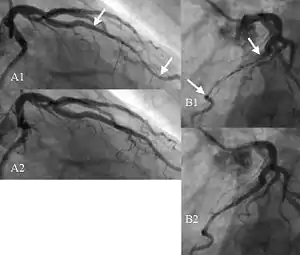

| Angiogram showing myocardial bridging resulting in arterial compression. |